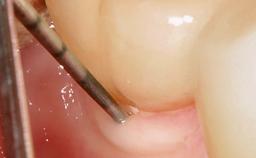

Despite anti-infective surgical treatment, some patients may experience recurrent infection and progressive bone loss requiring additional treatment. Removal of Implant Due to Recurrent Infection describes a conservative approach using an implant retrieval tool without the need for excessive bone removal or use of a trephine.

A 70-year-old female patient was referred by her general dentist to the periodontist for assessment and management of an infection associated with implant 36. The general dentist had noted suppuration on probing during examination.